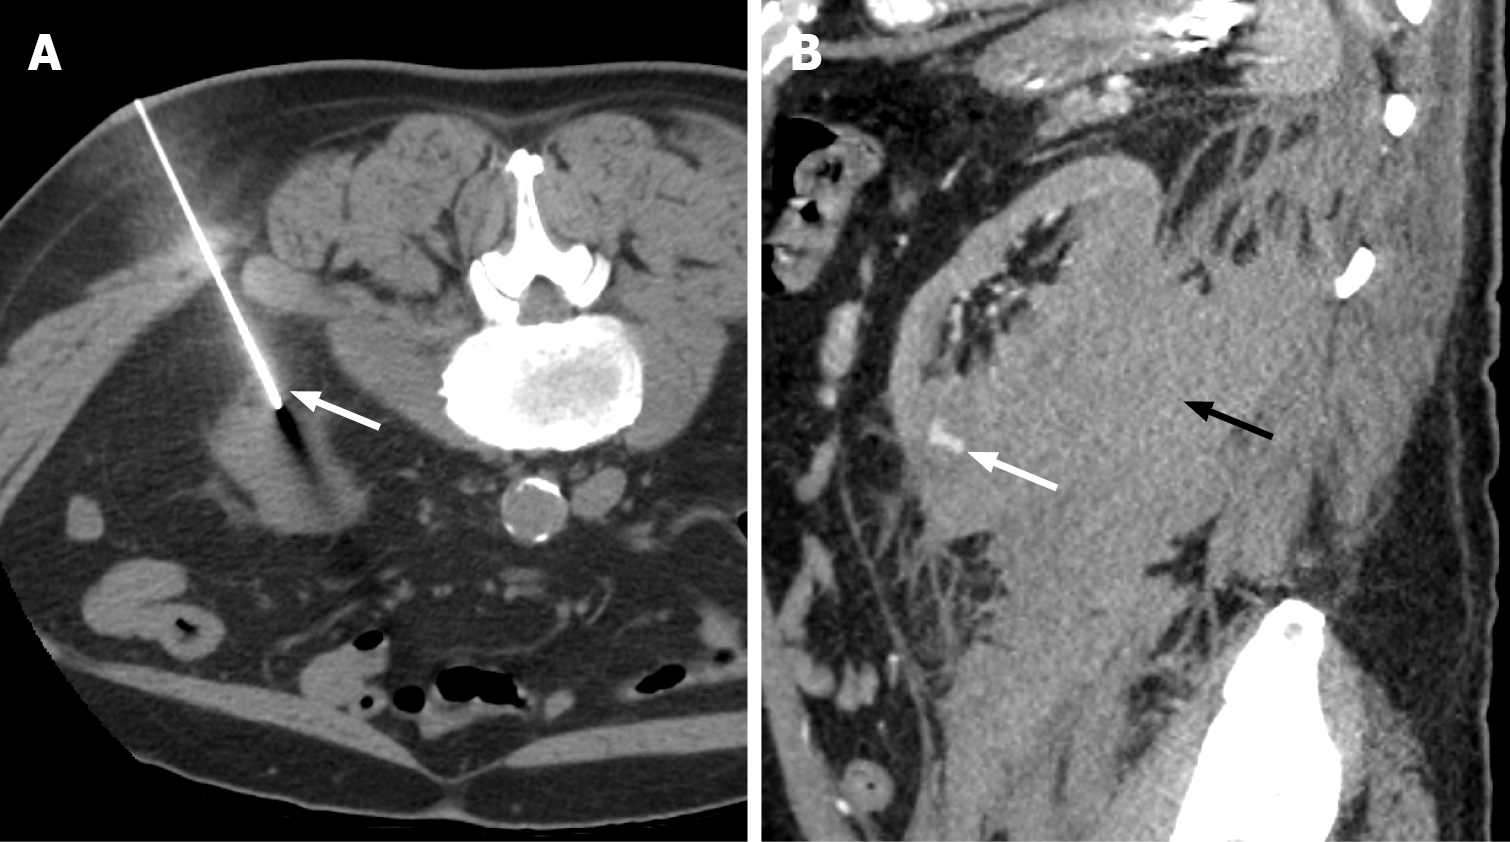

Figure 4 Grade IV renal injury.

A: Axial computed tomography of the abdomen in corticomedullary phase demonstrating renal hilar injury with diffuse hypoattenuating fluid collection in the hilum, concerning for collecting system involvement (white arrow); B: On delayed phase imaging, note the contrast extravasation from the renal collecting system into the hypoattenuating collection consistent with urine extravasation (white arrow). These findings correspond to grade IV renal injury.